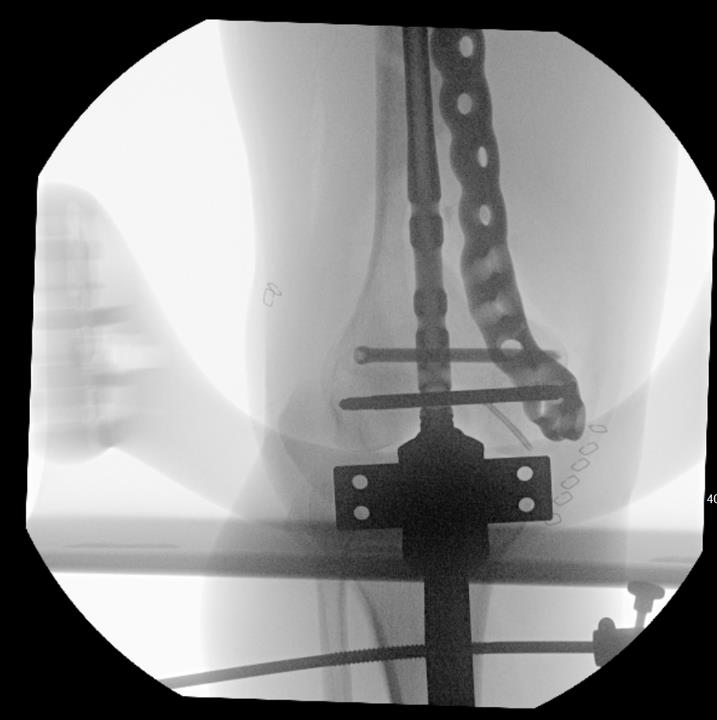

Summary Designed with SOMA (Stryker Orthopedics Modeling and Analytics) which includes a database with CT scans from hospitals across the world and state of the art algorithms that analyze shape variability, bone density, and implant fit Designed to link with the T2 Alpha Femur Retrograde Nail when using nail plate combination fixation Eight distal T20 screw holes, including 1 linking hole and 1 AP hole designed to capture Hoffa fragments Related Implants The Pangea® Femur Reconstruction System includes Lateral NPC Plate Medial NPC Plate (this topic) T2 Alpha™ Femur Retrograde Nailing System Design Tapered end allows for atraumatic submuscular insertion Staggered screw holes designed to enable surgeon to choose points of fixation and allows for placement of screws around an intramedullary implant or a prothesis AP hole screw hole trajectory that is designed to capture a "Hoffa Fragment" (Posterior Medial Condyle) Variable-angle screw holes circular universal holes accept non-locking screws, and locking screws within a 30° cone Proximal twist metadiaphyseal twist allows for screw placement anterior to posterior Linking hole designed to allow for seamless linking of the plate to a T2 Alpha Femur Retrograde Nail using an AlphaLink Dowel Indications Indications partial articular medial tibial plateau fractures medial plateau fragments in bicondylar tibial plateau fractures metaphyseal fractures epiphyseal fractures extra-articular proximal tibial fractures Contraindications active or suspected infection at the surgical site severe local inflammation around the operative area hypersensitivity or allergy to implant materials inadequate soft-tissue coverage over the implant Anatomy Osteology medial tibial plateau medial femoral condyle intercondylar eminence attachment point for cruciate ligaments tibial tuberosity insertion of the patellar tendon Muscles anteromedial tibia sartorius gracilis semitendinosus popliteus stabilizes and unlocks the knee Ligaments medial collateral ligament anterior cruciate ligament posterior cruciate ligament medial meniscus Approach Surgeons may use a standard medial, medial parapatellar, or medial subvastus approach to the distal medial femur Technical specifications Plate material type II anodized titanium (Ti6Al4V) Two plate lengths 155mm and 265mm Plate thickness 5mm Left and right anatomic options Screws Multiaxial locking 5.0 (14-120 mm) 4.0 (14-95mm) 5.0 (10-20mm) Cortex 4.5 (14-150mm) Cancellous 6.0 (20-150mm) 6.0 (30-150mm) 6.0 (45-150mm) Cable plug washer AlphaLink Dowel 50-90mm